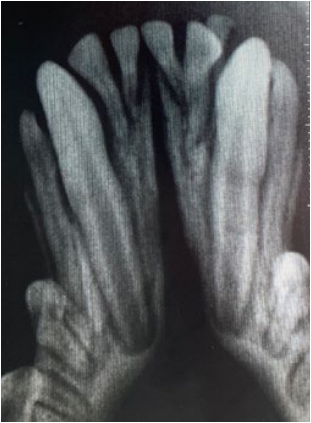

- Метаболические нарушения (такие патологии, как гипотиреоз и вторичный гиперпаратиреоз). На фото 4 представлен пациент – кошка (возраст – 1 год и 1 месяц), у которой сохранены временные 707, 807 зубы. Рентгенографическое исследование того же пациента (фото 5–7) выявило резорбцию зубов, незавершенные апексы, периодонтит, наличие ретенированных предшественников 307 и 407 зубов.